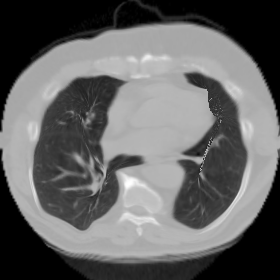

7.3. Real CT images

We now consider applying the proposed image registration method on real lung CT images retrieved from the National Lung Screening Trial (NLST) dataset [1]. Fig. 9(a) and Fig. 9(b) show two slices of lung CT images that we use as the source and the target (see Fig. 9(c) for the absolute intensity difference). We remark that the CT images are originally with different intensity, and so we apply an intensity histogram matching before running the registration experiment. Fig. 9(d) shows the registration result obtained by our proposed method. It can be observed that our method successfully produces a large deformation on the right lung of the source image to match that of the target image (see also Fig. 9(e) for the final absolute intensity difference). On the contrary, DDemons [47] (Fig. 9(f)), LDDMM [5] (Fig. 9(g)), Elastix [29] (Fig. 9(h)) and DROP [18] (Fig. 9(i)) all fail to produce an accurate and bijective registration result. This shows that our method is more capable of handling large deformation image registration.

We then test our method on slices of chest CT images obtained from the Open Access Biomedical Image Search Engine [2]. Fig. 10(a) and 10(b) show the source image and target image respectively, and the intensity difference is shown in Fig. 10(c). The registration result obtained by our proposed method is shown in Fig. 10(d) (see also the result with the deformed underlying grid in Fig. 10(e)). From the final intensity difference plot in Fig. 10(f), it is easily to see that our method matches not only the two large components but also the small dot at the center very well. On the contrary, DDemons [47] produces a suboptimal registration result with a significantly larger mismatch of the small component at the center (see Fig. 10(g) and Fig. 10(h)).